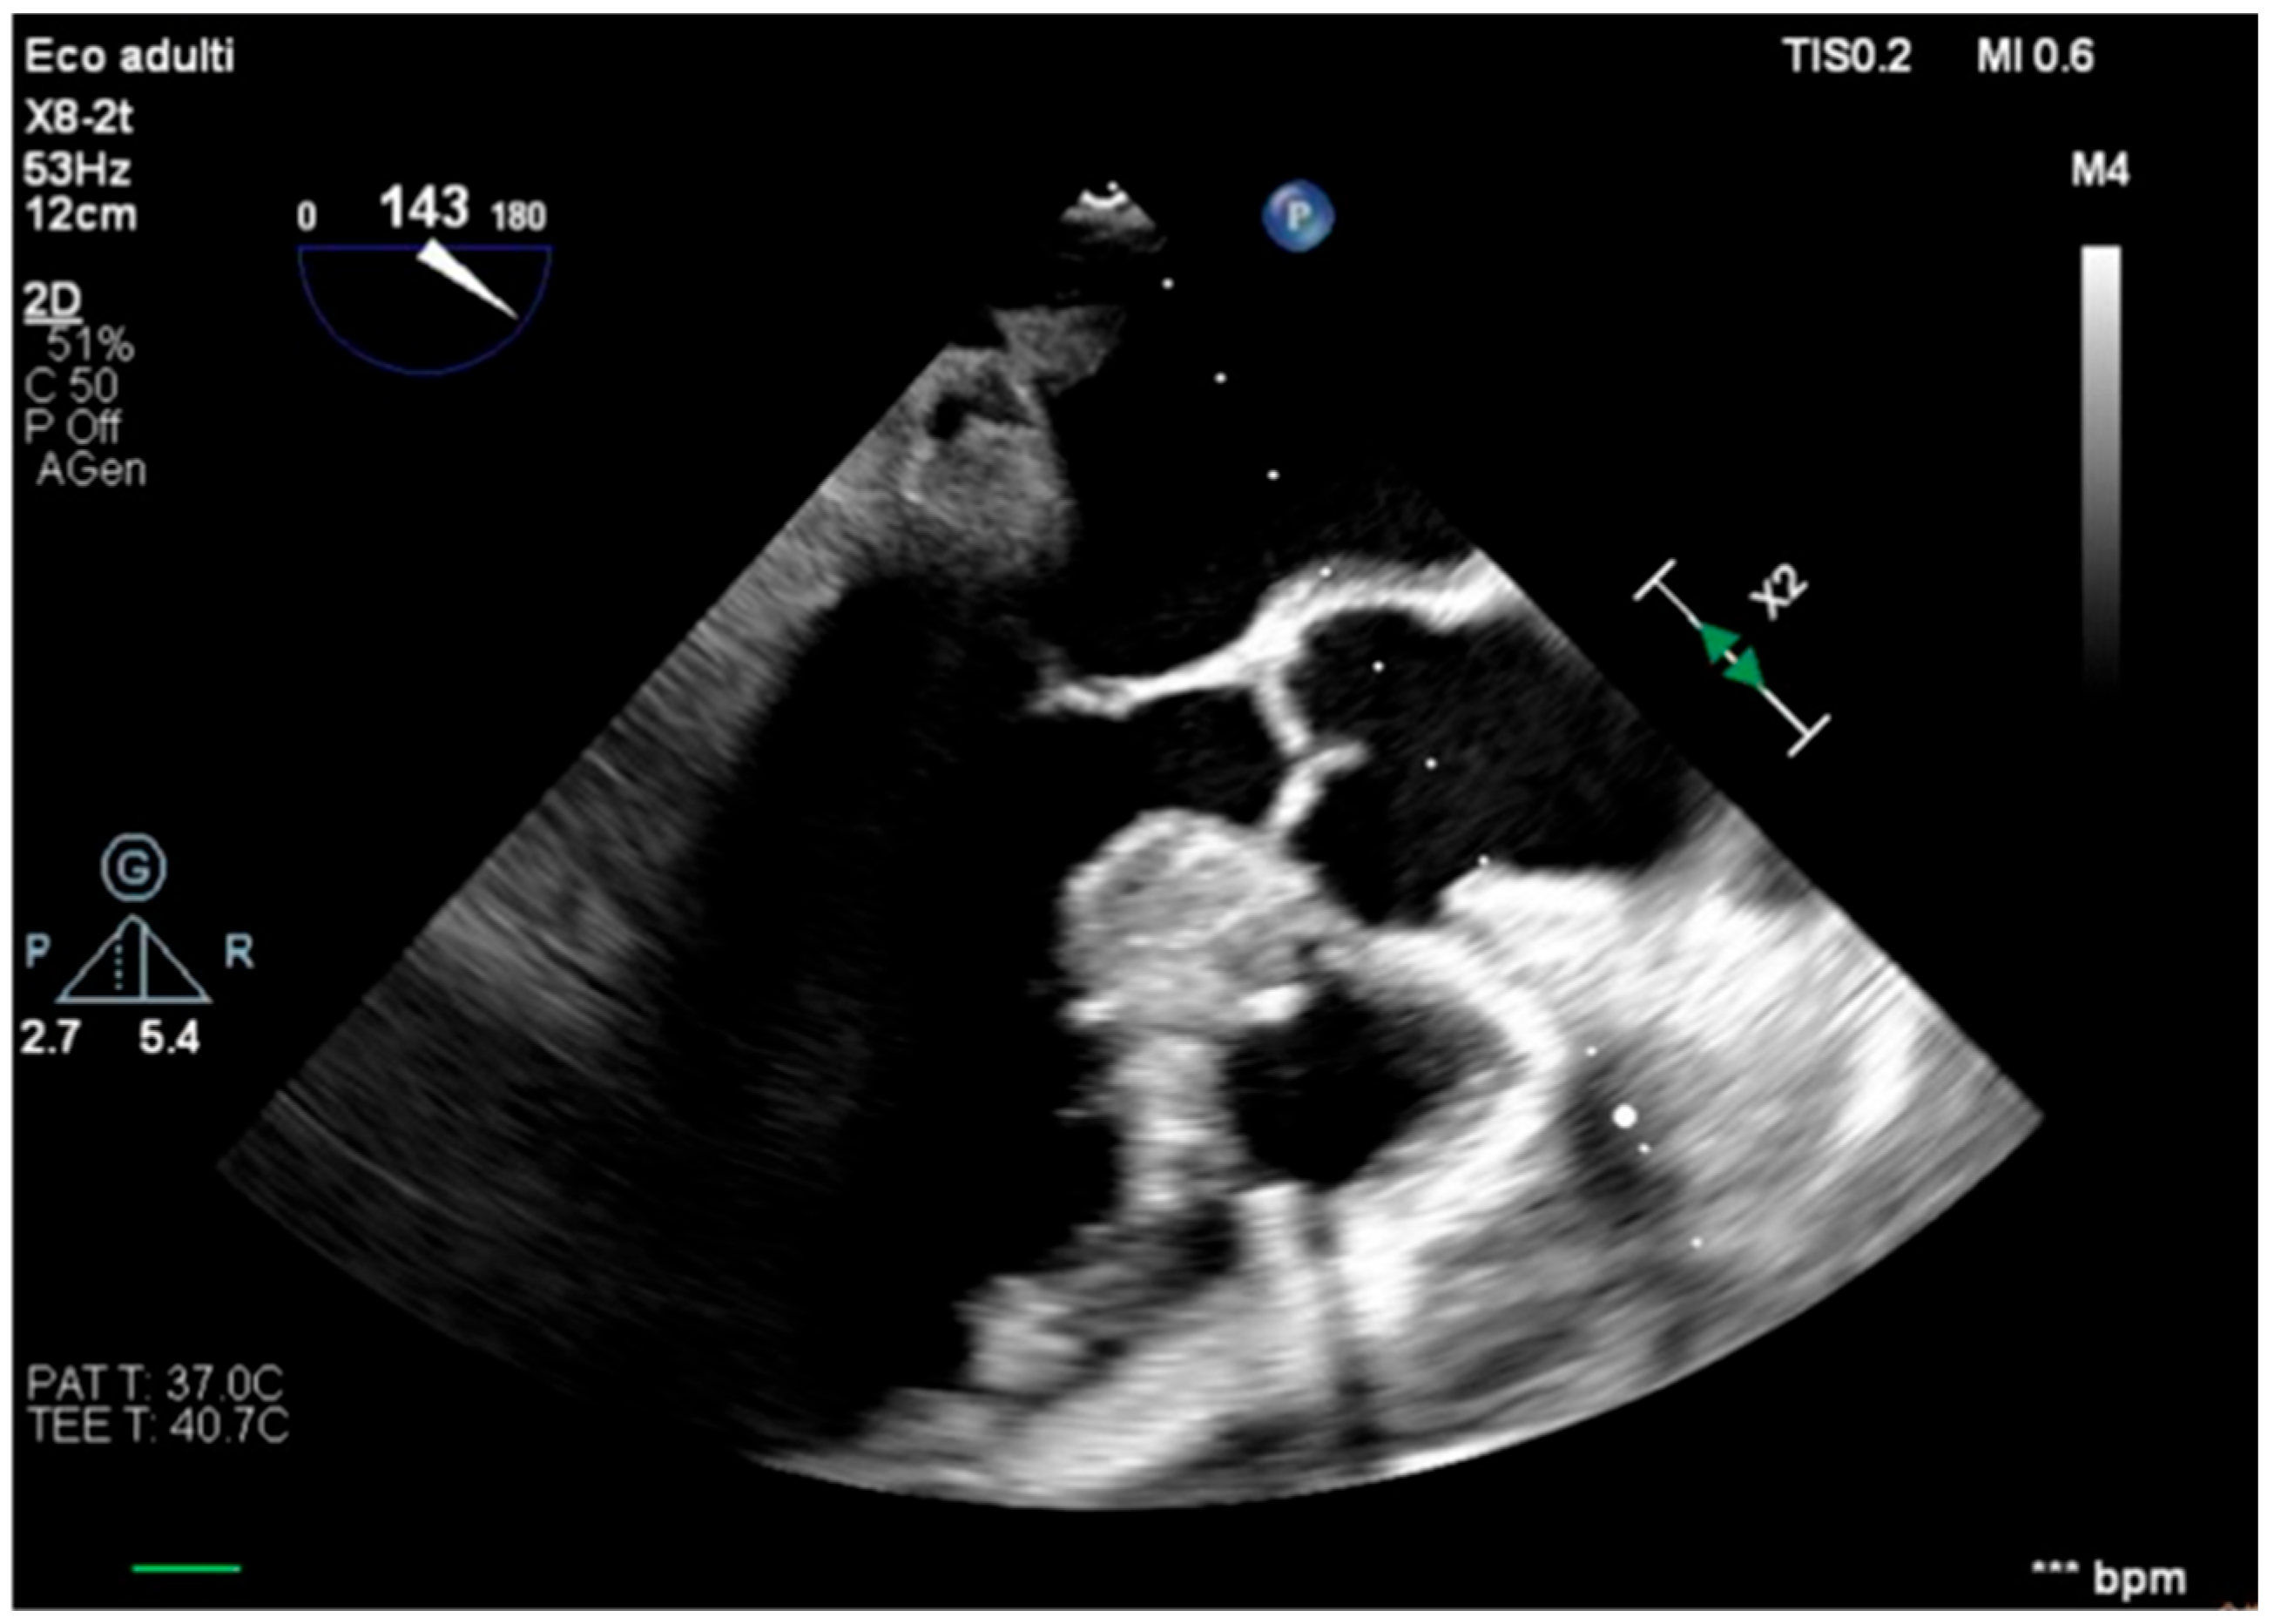

The transesophageal echocardiography showed LVOT-VTI 10 cm; apical, septal, and anterior wall akinesia; preserved function of the medium-basal segments of the inferior and lateral walls (Figure 3, Figure 4 and Figure 5); and RV-FAC 39% with an unloaded right ventricle (Figure 6).

Figure 4. Long-axis view, improved function of the inferior–lateral wall.